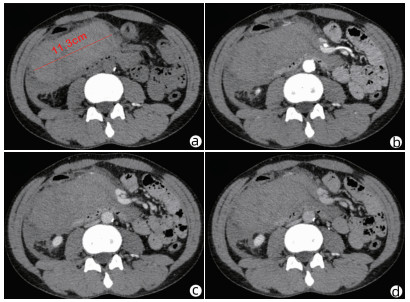

Clinical effect of simultaneous surgical resection of hepatic and pancreatic lesions versus systemic chemotherapy in treatment of resectable pancreatic cancer with liver metastasis

Tianqiang JIN, Chaoliu DAI, Feng XU

2022, 38(3): 622-628. DOI: 10.3969/j.issn.1001-5256.2022.03.023

Abstract(1384) HTML (1170) PDF (2734KB)(54)

Abstract:

Objective  To investigate the clinical effect of simultaneous surgical resection of hepatic and pancreatic lesions versus systemic chemotherapy in treatment of resectable pancreatic cancer with liver metastasis (PCLM).  Methods  A retrospective analysis was performed for related data of the patients with PCLM who were admitted to Shengjing Hospital of China Medical University from January 2013 to May 2020, and the patients with resectable PCLM were screened out and then divided into surgery group and chemotherapy group. The propensity score matching (PSM) method was used to reduce the impact of data bias and confounding factors. The independent samples t-test or the Mann- Whitney U test was used for comparison of continuous data between two groups, and the chi-square test was used for comparison of categorical data between two groups. The Kaplan-Meier method was used to calculate survival time, and the log-rank test was used for evaluation. The univariate and multivariate Cox regression models were used to investigate the independent risk factors for survival.  Results  A total of 56 patients with resectable PCLM were screened out, with 33 patients in the surgery group and 23 patients in the chemotherapy group, and there were 15 patients in each group after PSM. The surgery group had a significantly shorter median overall survival time than the chemotherapy group before PSM (6.6 months vs 10.4 months, χ2=4.476, P=0.034) and after PSM (6.4 months vs 10.5 months, χ2=4.309, P=0.038). The multivariate Cox regression analysis showed that poorly differentiated tumor (hazard ratio [HR]=4.945, 95% confidence interval [CI]: 1.980-12.348, P=0.001) and absence of postoperative chemotherapy (HR=3.670, 95%CI: 1.437-9.376, P=0.007) were independent risk factors for poor prognosis in patients with PCLM.  Conclusion  Compared with chemotherapy, simultaneous surgical resection of hepatic and pancreatic lesions fails to prolong the overall survival time of patients with resectable PCLM. Patients with poorly differentiated tumor and those without postoperative chemotherapy tend to have poor prognosis.